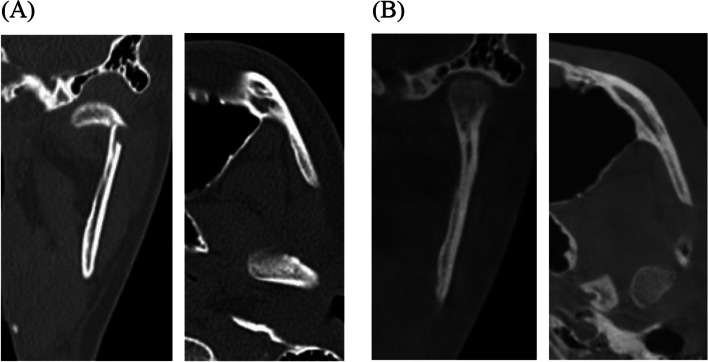

Methods: This retrospective study included 31 patients with unilateral mandibular condylar fractures treated non-surgically at the Ajou University Dental Hospital between 2005 and 2023. Computed tomography was performed at the time of the fracture (T 0) and > 6 months after non-surgical treatment (T 1). The extent of recovery of the highest point of the condyle head was measured in three-dimensional x-, y-, and z-axes. At the last follow-up > 6 months after remodeling (T 1), the prognosis was evaluated by clinical examination of mouth opening limitation, malocclusion, deviation on opening, temporomandibular joint disorder (TMD), and facial asymmetry.